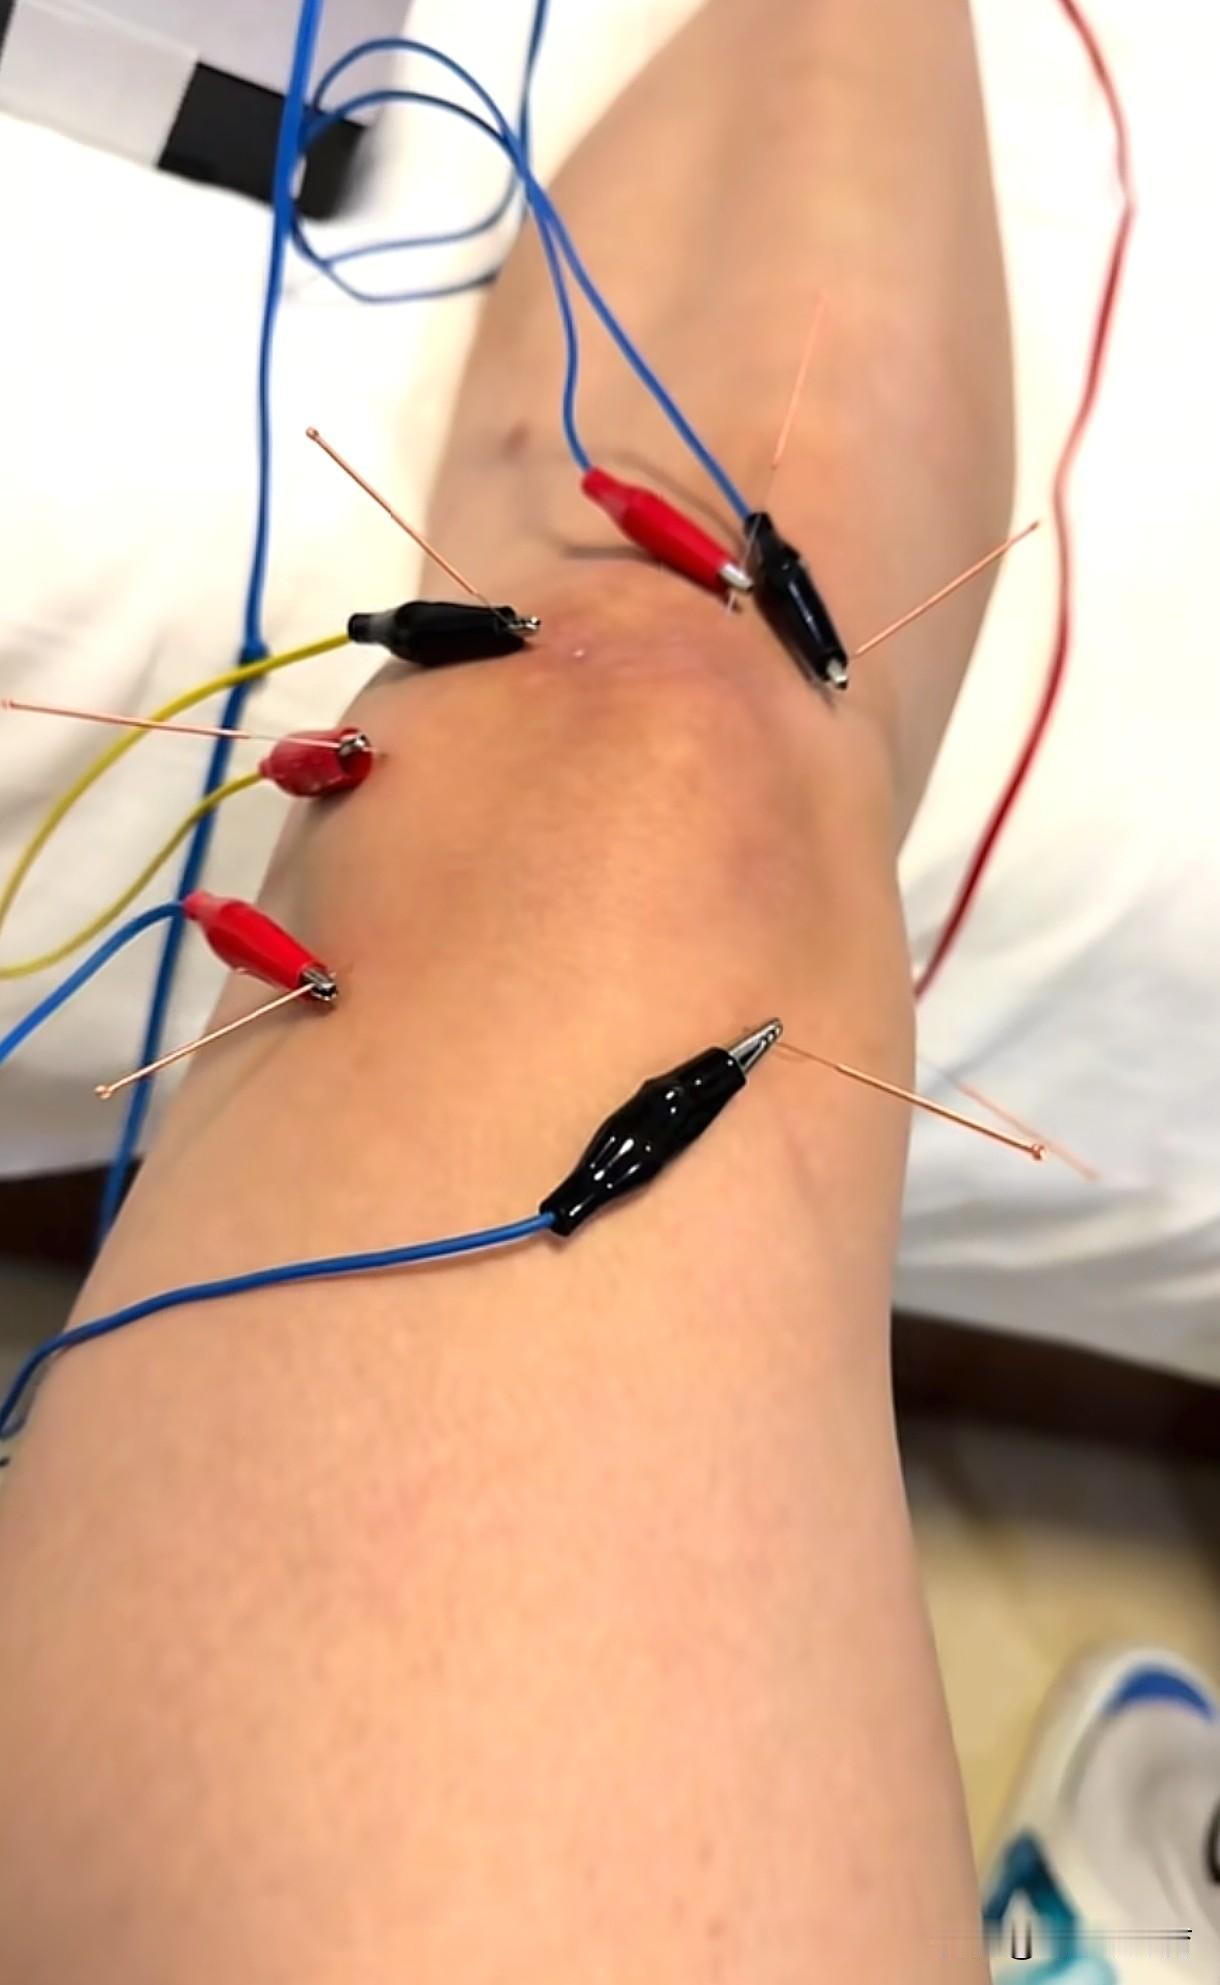

天津女排大将王艺竹透露自己打了封闭出战全运会。伤痕累累的王艺竹发布了自己的治疗和康复训练的图文视频,看了很心酸。当然,作为职业球员,这是常态,但她也不过是20多岁的小女生,却是一身伤病,甚至还打了封闭针出战比赛。封闭的副作用非常巨大,对于人体而言是不可修复的一种伤害,但是为了天津女排的成绩、回馈对于自己的培养,也是出于她个人的职业担当和态度,她毫不犹豫选择了承受和忍耐。如今的王艺竹是天津女排的中流砥柱,在李盈莹、王媛媛“留洋”之后,她和陈博雅将是天津女排的核心力量。距离新赛季联赛揭幕还有不到一个月的时间,王艺竹需要尽快康复,投入新的战斗。